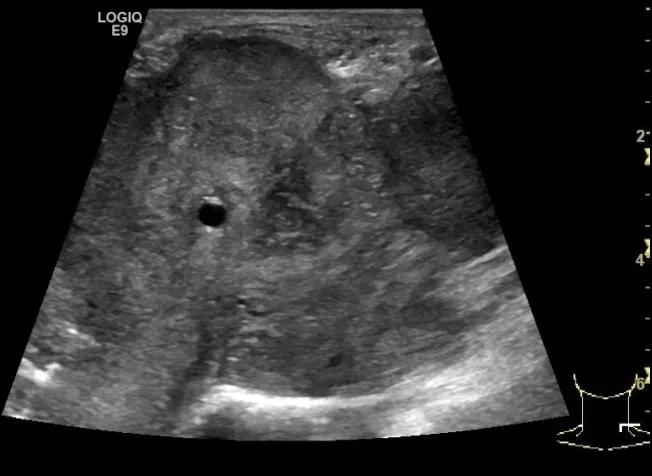

第二例是食管癌患者,术后半年余锁骨上固定淋巴结可触及肿大,疼痛非常明显,系统治疗后无缓解,患者希望通过局部处理缓解症状。造影显示强化信号明显,结节部分区域坏死,故主要针对强化区域从后向前的逐层的消融,皮下进行液体隔离减少烫伤。热消融后影像显示血流增强消失,弹性、硬度增高,一个月后复查显示充盈缺损,完全消融,疗效远超预期。

(病例2图例)